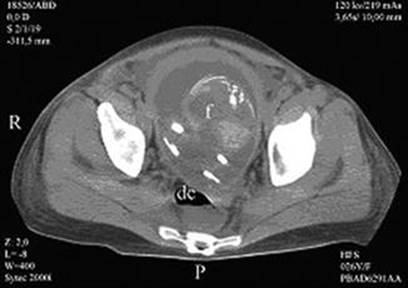

Fig. 3.10

Pregnant uterus (f fetus, dc Douglas collection) [111]

Fig. 3.11

Pregnant uterus (u uterus, fh fetal head, lc liquid collection) [111]